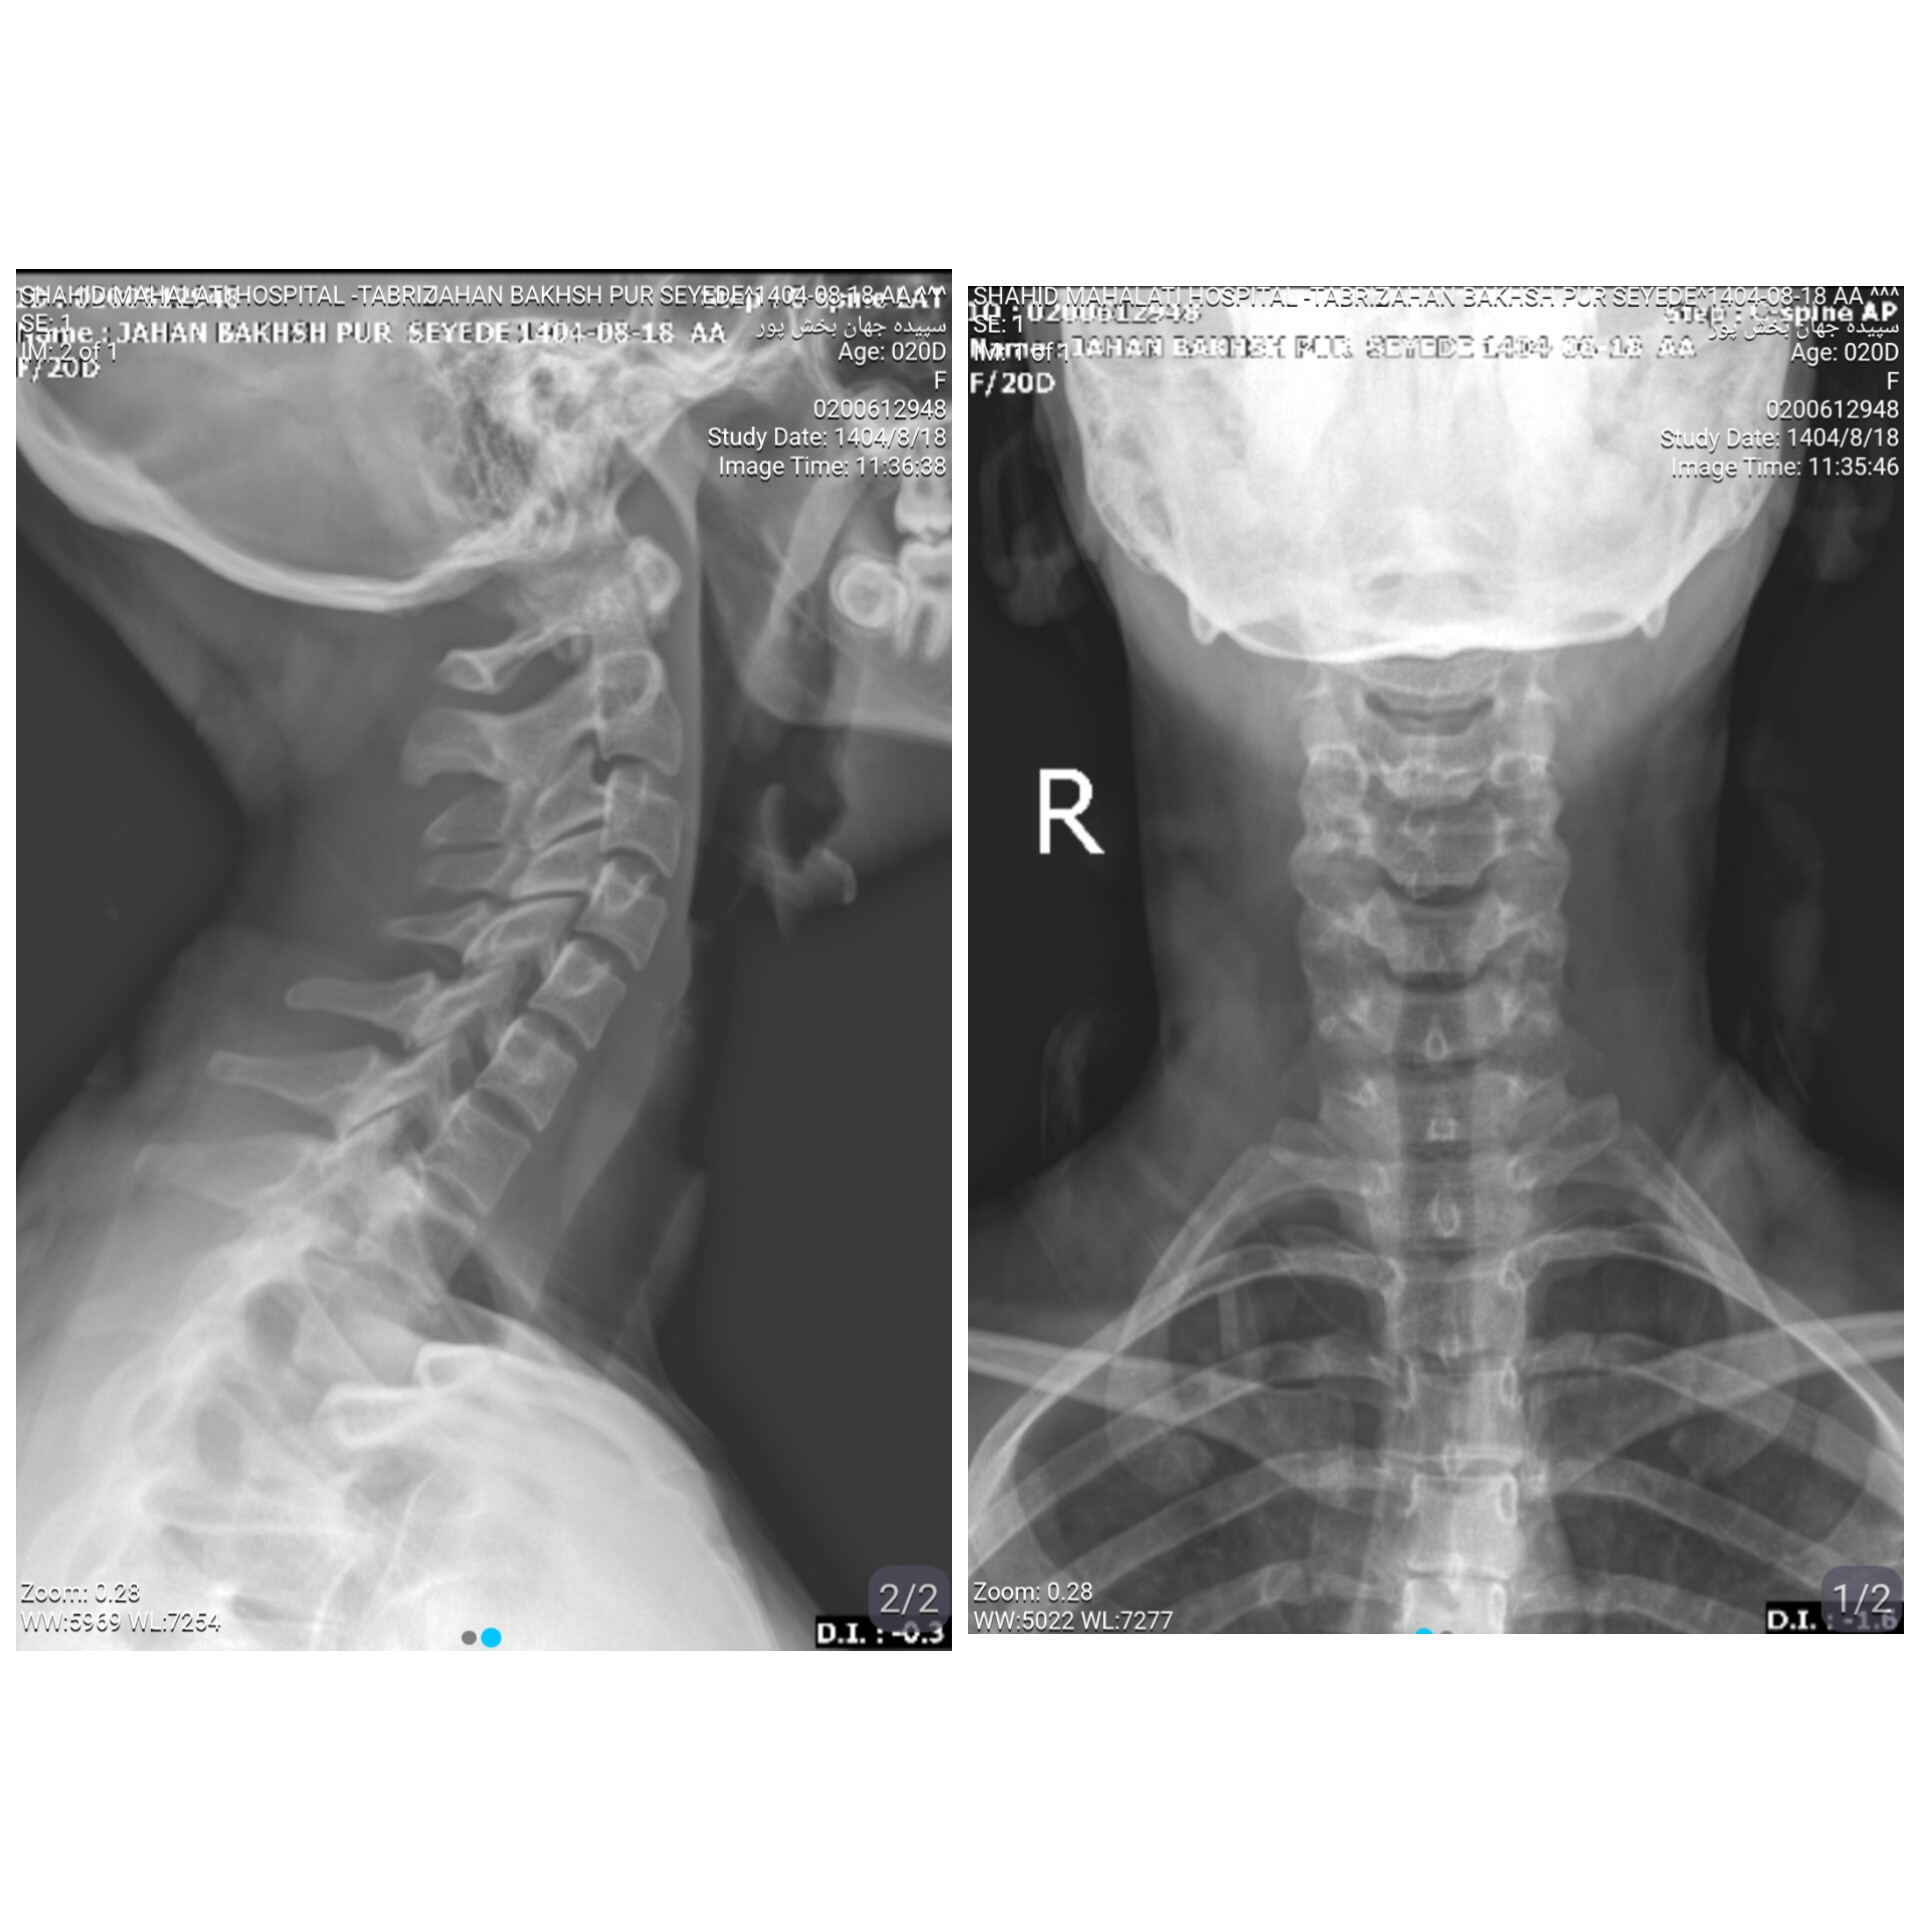

تشریح تصویر رادیولوژی گردن

سپی سن : 20 وزن : 40 قد : 159

سلام لطفا با توجه به تصویر ارسالی تشریح کنید و بگید مشکلی هس یا نه؟ بنده با شکایت از درد گردن و درد و ورم و گزگز شدید دست به خصوص دست چپ به دکتر مراجعه کردم.